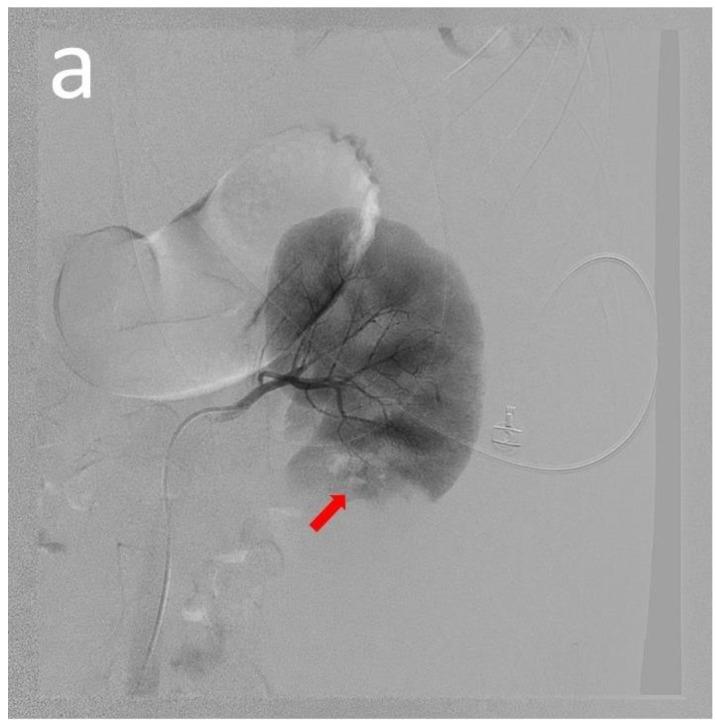

: Systemic lupus erythematosus (SLE) is a disease with multiple organ involvement, and spontaneous hemorrhage, especially perirenal hemorrhage, is rare. : We report the case of a 19-year-old teenager with SLE who experienced left flank pain and hypovolemic shock. Abdominal computed tomography revealed a large left retroperitoneal hematoma. Recurrent hypovolemic shock occurred despite the transcatheter arterial embolization of the left renal artery. Repetitive abdominal computed tomography results showed active hemorrhage. : An exploratory laparotomy was used to confirm descending colonic mesenteric artery bleeding, which was resolved. The patient needed temporary regular kidney replacement therapy for active lupus nephritis, which terminated one month after discharge. : When patients with SLE experience acute abdominal pain, flank pain, or back pain combined with hypovolemia, there is a higher risk of bleeding due to spontaneous hemorrhage, which should be included in the differential diagnosis. Therefore, early diagnosis and adequate emergency intervention are necessary.

系统性红斑狼疮(SLE)是一种多器官受累的疾病,自发性出血,特别是肾周出血较为罕见。我们报告了一例 19 岁的系统性红斑狼疮患者,其出现左侧腰痛和低血容量性休克。腹部 CT 显示左侧腹膜后血肿较大。尽管进行了左肾动脉的经导管动脉栓塞,但反复出现低血容量性休克。反复的腹部 CT 结果显示有活动性出血。剖腹探查证实降结肠肠系膜动脉出血,出血得到解决。该患者因活动性狼疮肾炎需要临时定期肾脏替代治疗,出院一个月后停止。当 SLE 患者出现急性腹痛、腰痛或背痛合并低血容量时,由于自发性出血,出血风险更高,应纳入鉴别诊断。因此,早期诊断和充分的急诊干预是必要的。